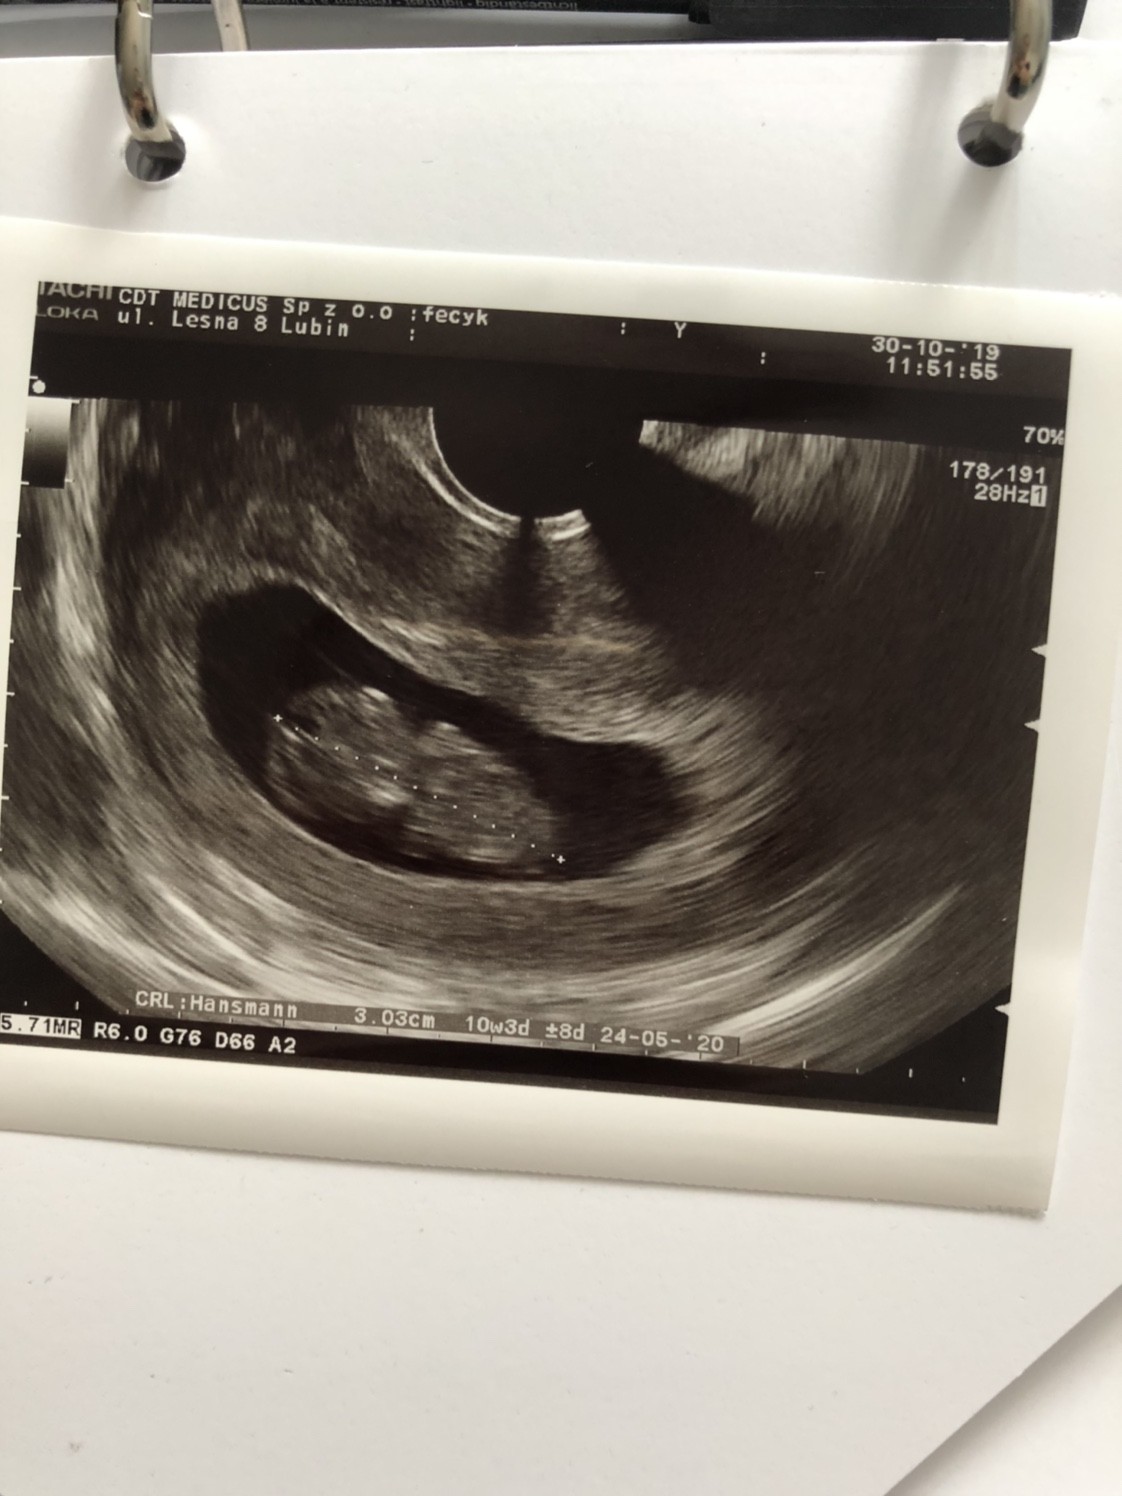

[emoji3525][emoji3525][emoji3525][emoji3525][emoji3525][emoji3525][emoji3525][emoji3525]Ja niestety również się żegnam, dzisiaj się dowiedziałam że serduszka przestały bić. Nawet nie wiedziałam, że to bliźniaki, ostatnio lekarz widział 1 a dzisiaj już 2.

Moja 3 strata i już więcej nie będę próbować, byłam obstawiona lekami i nawet to nie pomogło